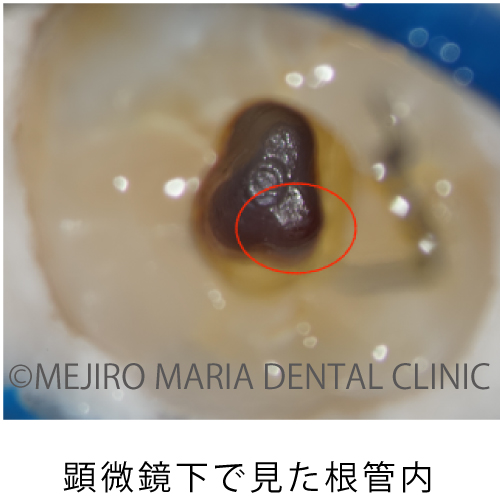

顕微鏡下で根管内を確認すると、レントゲン透過像通りに穴があいていること(穿孔)が確認され、実際の根管は治療が手つかずのままでした。